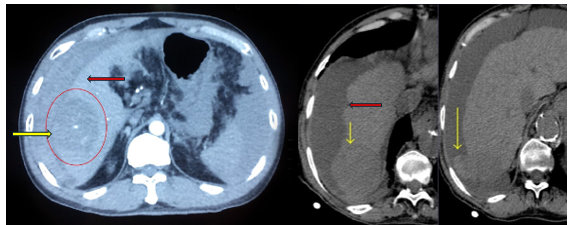

HCC vỡ  Đây là một biến chứng hiếm gặp nhưng đe dọa tính mạng với tỷ lệ tử vong cao (25%–75%). Cơ chế gây vỡ HCC vẫn chưa được làm sáng tỏ hoàn toàn. Tuy nhiên, sự kết hợp của nhiều yếu tố, bao gồm tăng áp lực trong khối u và bệnh lý mạch máu tại chỗ liên quan đến khối u ác tính, có thể liên quan đến nguy cơ vỡ

Triệu chứng của HCC vỡ bao gồm đau bụng đột ngột dữ dội tại vị trí u gan và các triệu chứng của hội chứng mất máu cấp, nặng hơn có thể có sốc mất máu. Siêu âm hoặc chụp cắt lớp vi tính có giá trị quan trọng trong chẩn đoán HCC vỡ

Xử trí HCC vỡ cần phụ thuộc vào tình trạng chảy máu và mức độ mất máu. Các phương pháp điều trị có thể bao gồm điều trị bảo tồn, TACE/TAE (Transarterial embolization) cầm máu hoặc phẫu thuật cắt gan. Bệnh nhân đang chảy máu nhưng không ổn định về mặt huyết động cần can thiệp cầm máu. TAE/TACE là một lựa chọn điều trị an toàn và hiệu quả để đạt được cầm máu ngay lập tức. Điều trị bảo tồn chỉ được khuyến cáo cho những bệnh nhân có huyết động ổn định và chức năng gan kém. So với chỉ can thiệp hoặc chăm sóc hỗ trợ, một phương pháp điều trị đa phương thức dưới dạng nút mạch và cắt gan theo giai đoạn có thể góp phần cải thiện khả năng sống sót

Hình 3: Khối u gan (mũi tên vàng) và tụ dịch bao gan do vỡ u (mũi tên đỏ) trên hình ảnh cắt lớp vi tính